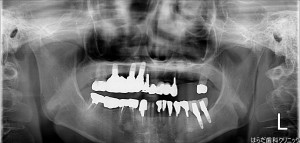

【左上4番、6番】インプラント2本埋入

本日、杉村先生によるオペが行われました。

患者様は先生によるオペが3回目でしたので、スムーズに行われました。

事前に何度も状態を確認して行われるので、患者様にも安心してオペを受けて頂けます。

患者様にも納得して頂き、先生を始めスタッフ全員で確認して準備やアシストを行なっています。